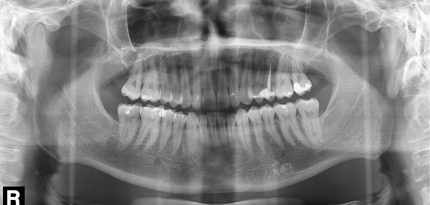

Orthopantomogram (OPG)

An OPG is a panoramic X-ray of the lower face, which shows all the teeth of the upper and lower jaws, as well as the surrounding bony structures (both maxillary sinuses, the nose, the cervical spine and the entire lower jaw and both jaw joints).